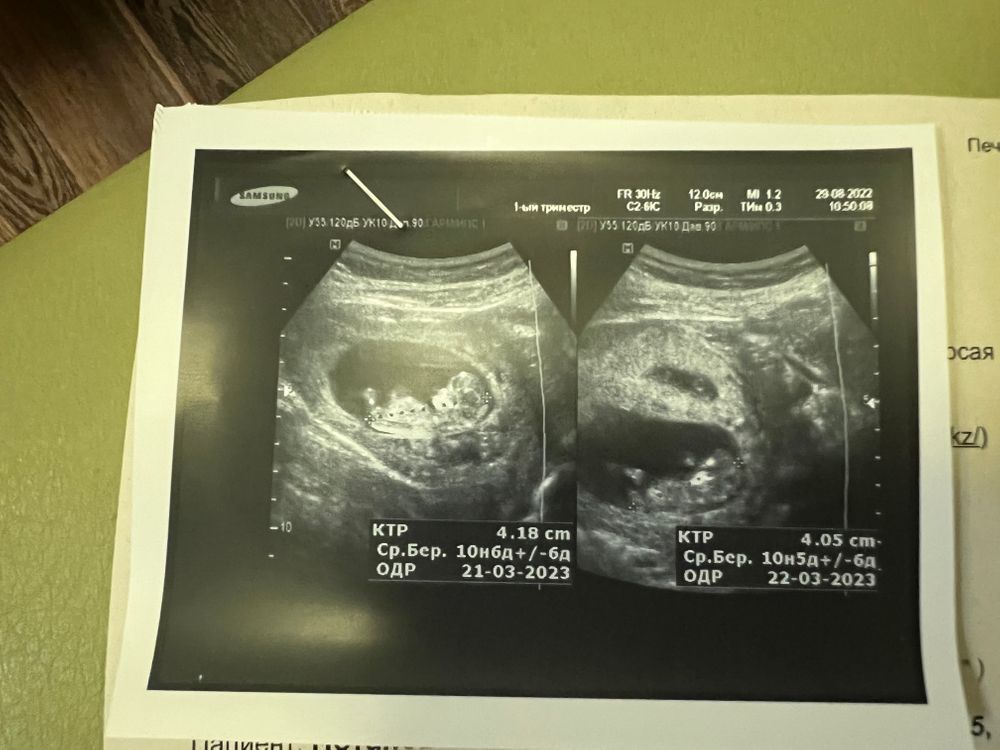

10+4 узи двойняшки